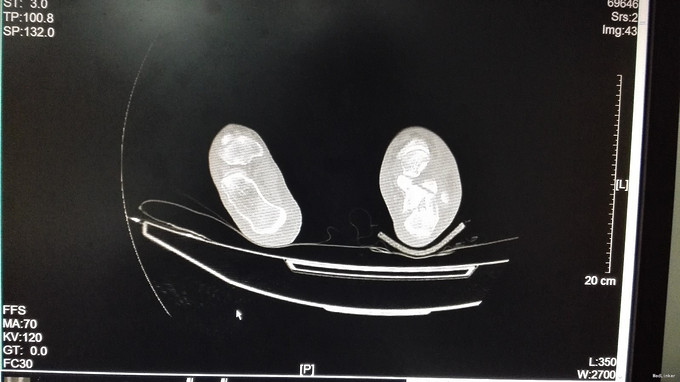

左足跟淤血肿胀明显,无明显畸形,皮肤完整,局部压痛明显,可扪及骨擦感,纵向叩击痛阳性,足趾活动正常,末梢血运、感觉正常。左跟骨X片示:左跟骨粉碎性骨折,左足部CT示:左侧跟骨粉碎性骨折,累及跟距关节面。

中年男性患者,因“跌倒致左足跟部疼痛、活动受限4小时”入院,左跟骨X片及左足部CT提示:左跟骨粉碎性骨折,累及跟距关节面。结合临床症状、体征及影像学检查,诊断左跟骨粉碎性骨折,且累及关节面,手术指征明确,排除手术禁忌后行切开复位内固定术,术后复查X片示对位良好。出院1月后复查,1月内避免负重。